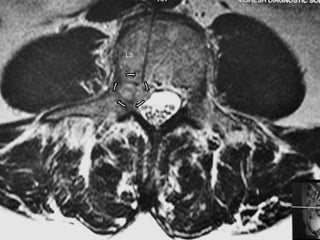

L3 l4 disc extrusion

Clinical examination • Testingof knee reflex and comparing with deep reflexes of other limb, click the possibility of neurological involvement. • Hence I asked for MRI. My patient had doubt in mind. His pain/discomfort was in/around knee and I am asking for MRI of spine!